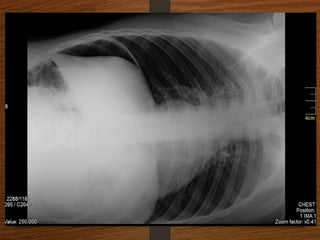

Sigmoid volvulus

The inverted U-shaped loop is usually massively distended

Commonly devoid of haustra, an important diagnostic point.

The ahaustral margin can often be identified overlapping respectively

 the lower border of the liver shadow (the liver overlap sign),

 the haustrated, dilated descending colon (the left flank overlap sign)

 the left side of the pelvis (the pelvic overlap sign).

The top of the sigmoid volvulus usually lies very high in the abdomen

(above the level of T10) with its apex on the left side.

Signs

 Grossly distended loop of sigmoid colon

 Coffee bean sign

 Air – fluid ratio > 2:1

 Lack of haustra

 Apex above 10th

thoracic vertebra

 Liver overlap sign

 Left flank overlap sign

 Pelvis overlap sign

 Bird of prey /twisted bird beak appearance

Doubt about the

diagnosis on the plain

radiographs

Contrast enema

• Features seen at the point of torsion include a

smooth, curved tapering of the colonic lumen, like a

hooked beak (the bird of prey sign)

• the mucosal folds often show a ‘screw’ pattern at the

point of twist